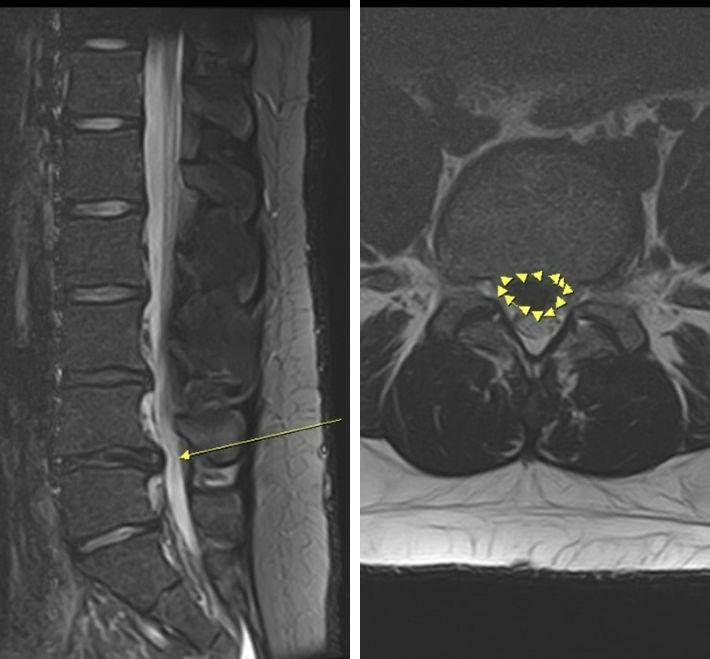

【脊椎滑脫最新全攻略】症狀原因、復健與手術時機:從第一級到第五級的精準治療建議

脊椎滑脫一定要開刀嗎?張建鈞醫師團隊詳解脊椎滑脫一至五級分級標準。研究顯示,多數一、二級患者可透過核心穩定運動與物理治療緩解。本文深度解析脊椎滑脫常見成因、間歇性跛行警訊,以及 2026 最新 3D 電腦導航微創手術趨勢,將植入誤差控制在 0.1 公分內,助您精準止痛、快速恢復生活品質。

【椎間盤突出】會自己好嗎?自癒機率與急性期緩解指南

椎間盤突出一定要開刀嗎?張建鈞醫師團隊根據 2026 最新醫學文獻,深度解析椎間盤突出成因與紅旗警訊。研究證實約 70% 突出有機會自行吸收!本文涵蓋非手術復健,到 3D 導航內視鏡手術的精準醫療趨勢,助您精確判斷最佳治療時機,擺脫坐骨神經痛,找回脊椎健康。

脊椎側彎怎麼辦?從自我檢查到非手術治療全指南

深入解析脊椎側彎的定義、類型、檢測方法與治療選擇,包含 3D 電腦導航與 OLIF 微創手術最新技術,讓您快速掌握病情與最佳治療時機。

脊椎翻修手術全攻略:當「再次手術」成為必要,如何控制風險?

脊椎手術後疼痛復發、鋼釘鬆脫怎麼辦?張建鈞醫師深度解析「脊椎翻修手術」。利用 O-arm 3D 導航精準避開神經沾黏與疤痕組織,搭配 OLIF 側開式微創路徑,大幅降低出血與風險。內含翻修原因分析、術後康復與常見問答,助您在安全保障下重獲生活品質。